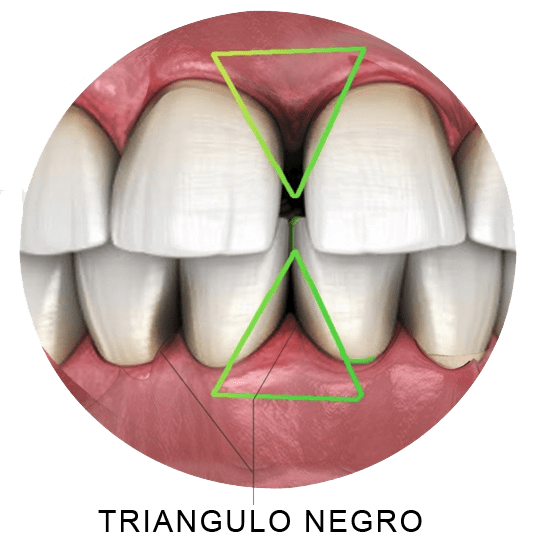

🌸Estética Gengival

Rosa Perfeita

👆 Toque para abrir

Rosa Perfeita

Nivelamento gengival, despigmentação (gengiva escura), reconstrução de papila (triângulos negros). A moldura perfeita para o seu sorriso.

O que é: Triângulos negros — perda da papila gengival (o triangulinho rosado entre os dentes). Causado por periodontite, recessão gengival ou tratamento ortodôntico que separou os dentes sem trazer a gengiva.

O que fazer: Avaliar a causa. Em casos periodontais, tratar a doença primeiro. Em alguns casos, enxerto de tecido conjuntivo pode reconstruir parcialmente a papila. Em outros, a solução é restauradora (facetas ou resina).